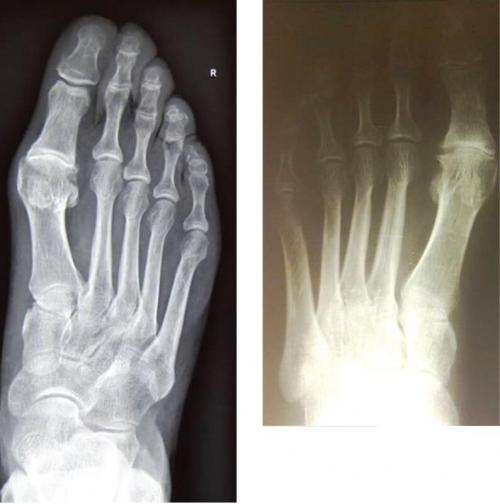

Одной из особенностей заболевания является возникновение значительных повреждений в суставе без видимых внешних деформаций, изменения положения первой плюсневой кости и основной фаланги первого пальца (у пациента с выраженной ригидной деформацией, может быть не больше первой степени поперечного плоскостопия и отсутствовать вальгусная деформация пальца). Все это значительно затрудняет диагностику. Точно выявить заболевание на всех стадиях позволяет только рентгенография стопы в стандартных проекциях (рис. 1). С целью оптимизации диагностики и результатов лечения мы считаем целесообразным поделиться нашим опытом.

Рис. 1. Рентгенограммы различных вариантов ригидной деформации I пальца

Среди пациентов Международного Центра Хирургии стопы, обратившихся за консультативной помощью с патологией переднего отдела стопы в период с марта 2012 по март 2017 гг., в 7,4% случаев диагностирован деформирующий артроз I плюснефалангового сустава III стади с формированием ригидного первого пальца стопы. Лечение таких больных имело свои особенности. При отказе пациента или невозможности выполнения оперативного лечения, а также в тех случаях, когда болевой синдром неинтенсивный и еще сохраняется небольшая амплитуда движений в первом плюснефаланговом суставе, мы считаем целесообразным применение консервативных методов лечения. Предписываются рациональные физические нагрузки и обувь, индивидуальные стельки (изготовленные с учетом характера заболевания) и специализированная лечебная физкультура. Регулярно проводятся курсы лечения имплантатами синовиальной жидкости. Препаратом выбора является «Ферматрон», созданный на основе гиалуроната натрия. Для консервативного лечения используется 1% раствор, выпускающийся в шприцах, содержащих 2 мл лекарственного вещества. Ферматрон вводят непосредственно в полость первого плюснефалангового сустава. После обработки антисептиками по внутренней поверхности первого пальца стопы пунктируют сустав, иглу вводят перпендикулярно поверхности. Ориентирами служат характерная кожная складка на уровне суставной щели и сухожилие разгибателя первого пальца, отступив книзу от которого, осуществляется доступ в полость сустава. Ферматрон восстанавливает вязко-эластичные и защитные свойства суставной жидкости, снижает воспалительные реакции, стимулирует синтез собственной гиалуроновой кислоты. В результате устраняется болевой синдром и увеличивается амплитуда движений в суставе. Ферматрон вводят 1 раз в неделю, курс лечения состоит из 4 инъекций и проводится 1 раз в год. В связи с небольшим объемом полости сустава, целесообразно вводить не более 1 мл препарата, при отсутствии опыта рекомендуется выполнять инъекции под контролем УЗИ. По нашим наблюдениям, данные курсы лечения позволяют отсрочить оперативное лечение сустава до 5 лет. Обязательны ежегодные осмотры пациента с выполнением рентгенографии стопы для своевременного выявления возможного прогрессирования заболевания.